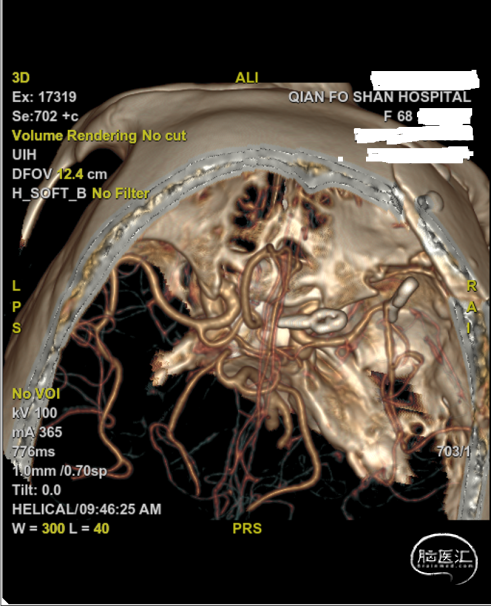

入院后行DSA检查,显示右侧颈内C6-7段动脉瘤右侧大脑中动脉M1分叉动脉瘤。

C6-7段动脉瘤位于颈内动脉上壁,指向内上方,考虑血泡样动脉瘤,结合蛛血位置,及动脉瘤形态、大小,考虑颈内动脉血泡为责任动脉瘤。

术后10天复查CTA: